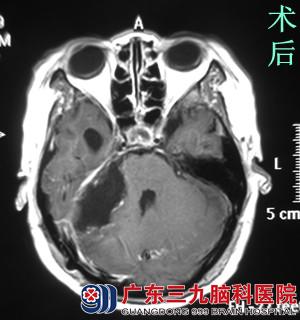

查体发现:潘女士神志清醒,右眼眼裂较左侧小,右眼睑下垂,睁眼乏力,右侧额面部触觉、痛觉、角膜反射明显减弱,右侧侧额纹、鼻唇沟变浅,嘴角向右偏斜,右侧皱眉、闭眼乏力,悬雍垂右偏,咽反射减弱。行头颅MR检查提示右侧桥小脑角区示一团块状占位病变,大小约6.29*4.29*2.37cm,相邻脑组织(脑干及右侧小脑半球)明显受压。

完善相关检查后,鲁明主任带领他的神经外科团队讨论。由于潘女士同时存在两个问题:脑肿瘤、面肌痉挛,考虑两个病变都在同一侧,最后一致决定一次手术解决两个问题。7月18日,由鲁明主任主刀,在全麻下行右侧CPA区巨大占位性病变切除术+右侧三叉神经微血管减压术。术中见肿瘤位于右侧桥小脑角区,黄白色,实性,质韧大小约5.5*5.8*4.9CM,术中电生理监测,予显微镜下电凝及超声刀分块切除,完整保留听神经、面神经、三叉神经、舌咽神经。术中见三叉神经周围蛛网膜粘连明显,予分离松解,见右侧小脑前下动脉分支明显压迫并包绕三叉神经,垫入Teflon棉,将血管与三叉神经隔离,并以生物胶固定,手术顺利结束。术后潘女士未见面部抽搐,术后症状均明显较术前好转。术后病理结果为:砂粒体型脑膜瘤(WHO I 级)。